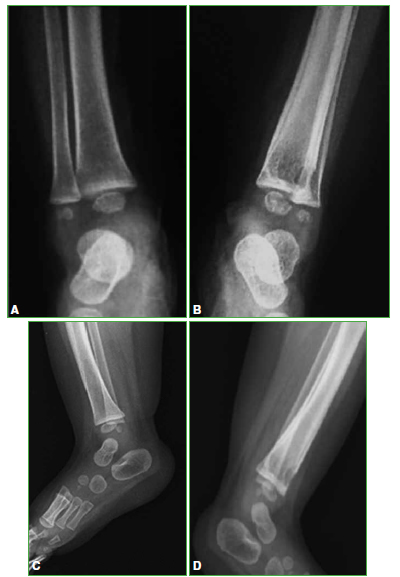

Tibia osteomyelitis secondary to BCG vaccination in an immunocompetent infant. Case report

Introduction: The Bacillus Calmette-Guérin (BCG) vaccine, used to prevent severe forms of tuberculosis (TB), is the most extensively used vaccine worldwide. Adverse events associated with BCG vaccination are rare, and most of them occur at the inoculation site. We present a tibia Osteomyelitis case secondary to BCG vaccination in an immunocompetent infant.

Conclusions: Bone involvement secondary to BCG vaccination in previously healthy patients is extremely rare. Healthcare providers must consider such settings in order to make the diagnosis and institute the appropriate treatment. Antituberculous drugs produced good therapeutic results with no need for surgical toilette.